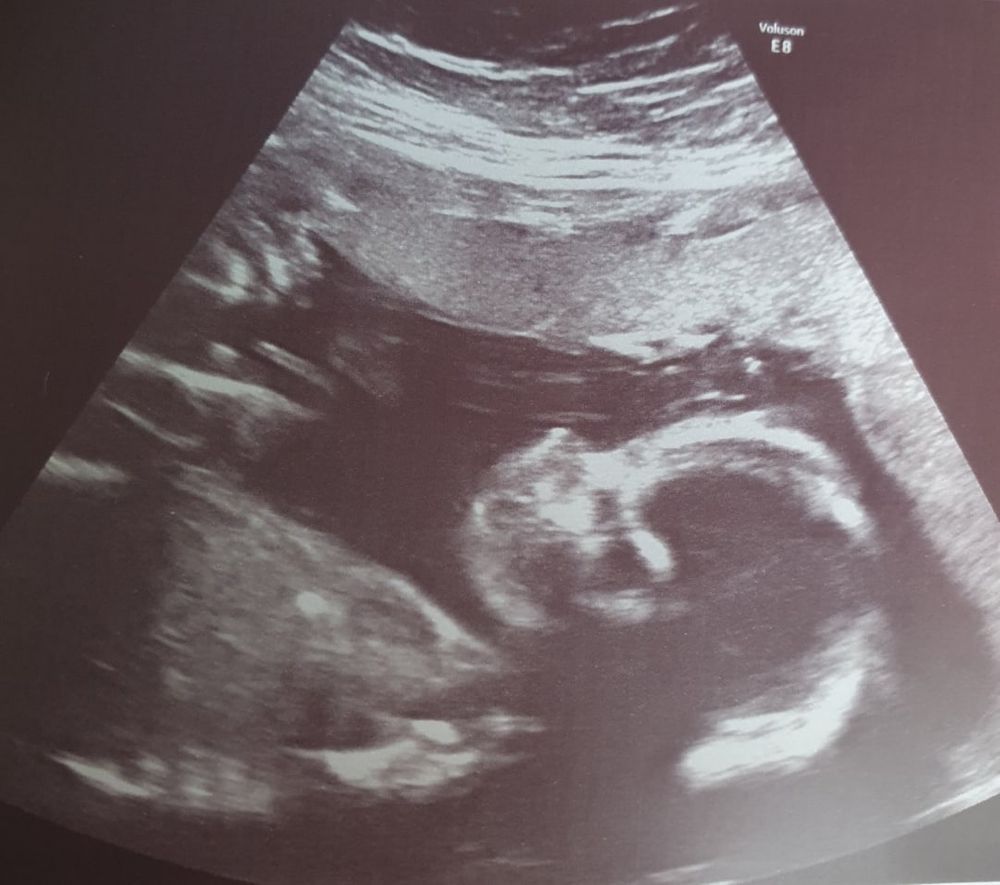

Прошли 3ий скрининг, все хорошо, малышка растет😊Сделали фото, долго пробовали, думала уже уйду без него, но все получилось. Это первый именн